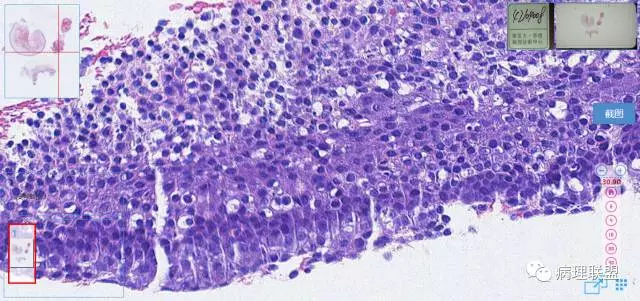

第一例

第一例和第二例病例我把典型图像压下来,是让我们以后注意,典型里找不典型,毛母质瘤主要由两种细胞构成,嗜碱细胞和影细胞构成,主要认识嗜碱细胞。

左老师,开始发的图片没有看到影细胞。最后加的图才看到了